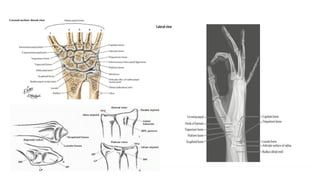

ANATOMY OF THE WRIST JOINT

The wrist joint aka the radiocarpal joint connects and serves as a transition point between the forearm and hand.

1. Type of Joint; A Condyloid Synovial Joint i.e. a modified ball and socket joint that allows for flexion,

extension, abduction, and adduction movements.

2. Articulations; The joint itself is formed through the articulations between the distal radius and the scaphoid,

lunate, and triquetrum. The distal radius is responsible for 80% of axial load & articulates with scaphoid via

scaphoid fossa & lunate via lunate fossa. The ulna is not part of the wrist joint itself, as it articulates with the

distal radius via the distal radioulnar joint (DRUJ) at the ulnar/sigmoid notch.

3. Ligaments; The four ligaments responsible for maintaining the stability of the joint are

● Palmar and dorsal radiocarpal ligaments

● Ulnar and Radial collateral ligaments.

4. Innervation;

● Median nerve: Via the anterior interosseous branch

● Radial nerve: Via the posterior interosseous branch

● Ulnar nerve: Directly through its deep motor branches

5. Blood Supply; Via ulnar and radial arteries, through penetrating branches from the dorsal and palmar carpal

arches